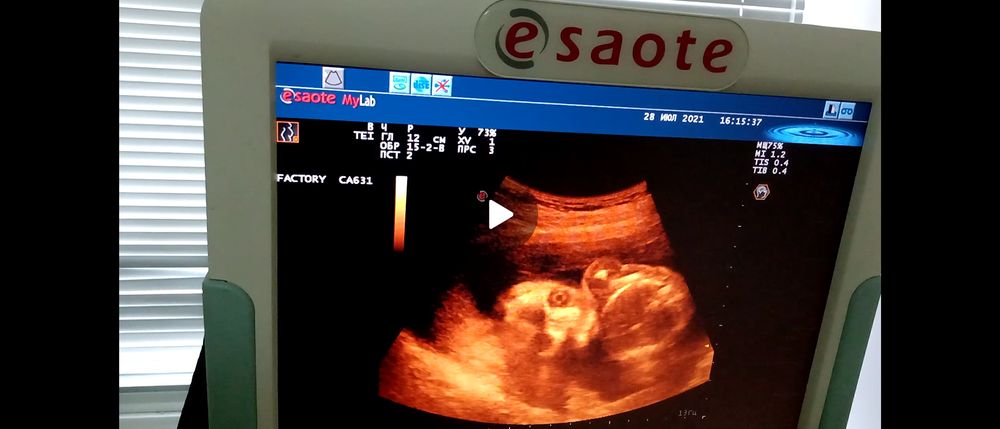

2 скрининг

Пол малышаНу что, я снова тут, срок уже 20.1, сегодня прошли второй скрининг и нам подтвердили девочку) у мужа это уже будет третья, и опять зимняя доча) я прям даже немного расстроилась, хоть и знаю, что мужу все равно какого пола ребенок. Я старалась до этого особо не думать о том, какого пола малыш, чтобы не настраиваться на кого-то определенного, но, скажем так, до того как я узнала жилось мне как-то проще)) не то чтобы я расстроена или не рада, но как-то не по себе) имя теперь думать, готовиться как-то... уже начинаю потихоньку осознавать, что там как бы уже человечище целых

390 грамм весом) На узи ещё и на старый аппарат попала, надо было срочно, потому что врач завтра в отпуск уходит, надо было ей показаться, а вариантов с более новыми аппаратами не было, но нам дали заснять видео, муж сказал что она похожа на робокопа, и лежит так же, как я сплю, в той же позе)) короче, когда деть лицом к датчику реально страшные фото выходят) лежит пока поперек, активно машет ручками-ножками, помахала в камеру всем привет) все в норме, чуть опережает срок, идеальная здоровая девочка, но низковата плацента. Прям сказал по краю внутр.зева, т.е.поберечься, и как то аккуратнее с половой жизнью, ну и на контроль через месяцок, посмотреть. Животика нет, малая в поперечном, сказал как чуть подрастет, станет скорее всего в продольное, начнет активнее расти живот, должна будет подняться и плацента, пока только ждать. Ну и готовиться морально к появлению еще одной дочки)